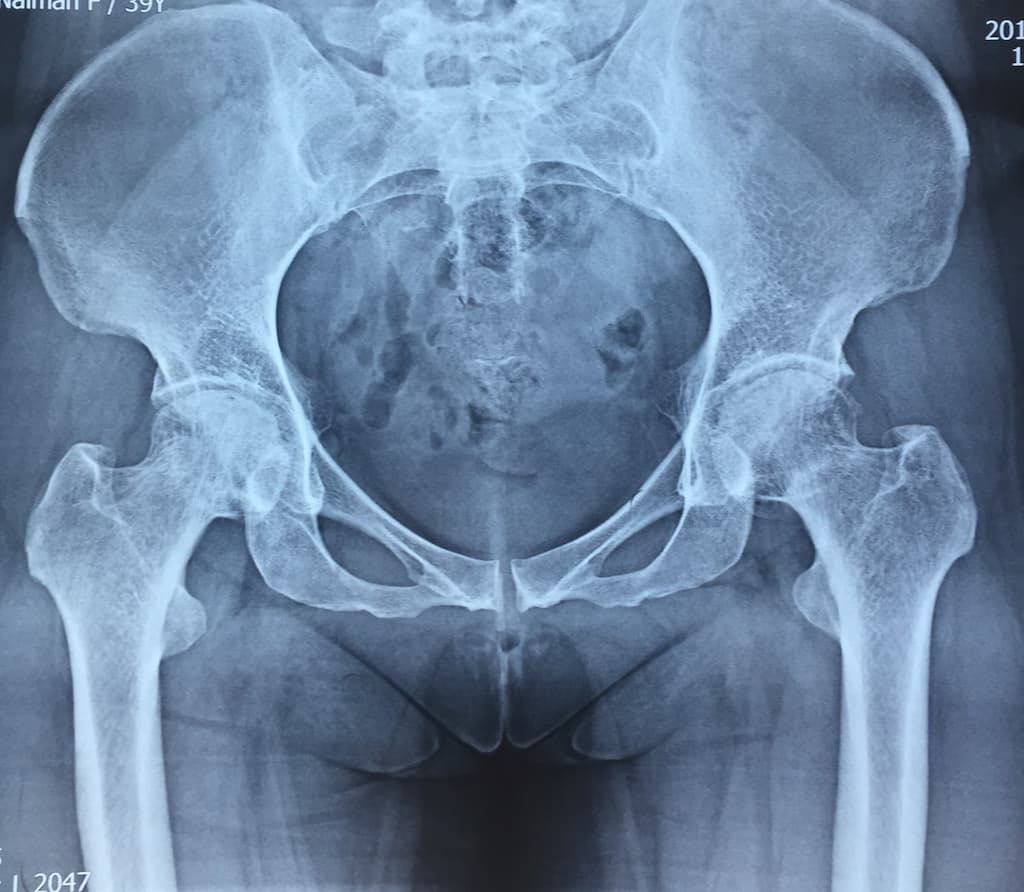

Түнхний үений төрөлхийн дутуу хөгжил

Нярай болон бага насны хүүхдийн хувьд түнхний үе төрөлхийн дутуу хөгжилтэй байх болон түнхний үений мултралттай тохиолдлууд байдаг. Нас биенд хүрсний дараа түнхний үений төрөлхийн өөрчлөлт нь артрит үүсгэх гол шалтгаан болдог бөгөөд хоёр хөл урт богино болж, аарцаг ясны тэгш хэм алдагдах болон түнхний үе мөн зэргэлдээх булчингын өвдөлт зовиур ихтэй болсноор хөдөлмөрийн чадвар муудаж, түүнчлэн тухайн хүний гоо зүй алдагдна. Иймээс түнхний үе солих мэс заслыг амьдралын чанарыг дээшлүүлэх, өвдөлт зовиур багасгах, хөлийн урт богиныг тэнцүүлж улмаар аарцаг ясны тэгш хэмийг хадгалах гоо сайхны зорилгоор хийж байна.

Мэс заслын өмнөх болон дараах рентген зураг